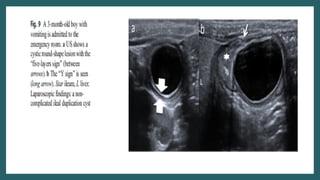

Ultrasound

• Typical gut signature sign present

• Wall is 2-3 mm thick

• Y sign(EDC share wall with adjacent GIT.

Caused by splitting of shared muscularis

propria between cyst and adjacent loop)

• Peristalsis present